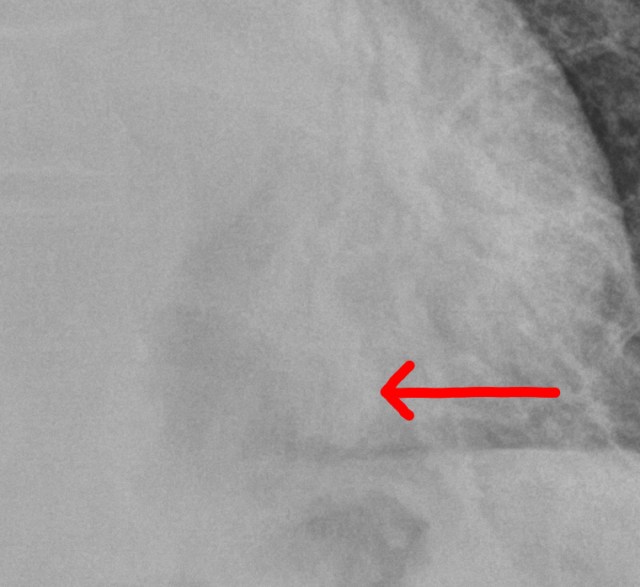

다시 맨 위의 사진으로 들어가서, 심장이 보이는 쪽을 잘 들여다 보면, 심장과 겹치는 부위에서도 폐혈관들이 가지를 치면서 나가는 걸 확인할 수 있습니다. 심장의 뒤쪽으로도 왼쪽 폐가 존재하기 때문에, 당연히 폐혈관이 심장과 겹쳐서 보이는건데, 보시면, 훨씬 안쪽에 보이는 폐혈관 윤곽이 이상하다는게 보입니다. 해부학 지식이 없어도 주변에 가지치며 뻗어나가는다른 혈관들과 윤곽이 다르다는걸 확인하는게 가능합니다.

아직까지 감을 잘 못잡으신 분들에게는 빨간색 화살표가 가르키고 있는 부위입니다. 폐 혈관이라는 게 두께가 일정하게 나가다 가지를 치면서 조금씩 가늘어지는게 정상인데, 해당 부위의 윤곽은 그렇지 않고 곤봉모양처럼 부풀어있거든요. 이건 폐혈관음영 주변에 폐의 공기가 아닌 다른 물질들, 이를테면 가래나 염증성 삼출물, 또는 암세포 같은 다른 물질들이 모여있어서 폐혈관의 윤곽을 가리고 있다는 걸 의미합니다. 이런 현상 또한 “실루엣 징후”라고 할 수 있는데, 실루엣징후에 대해 여기까지 예시를 보여주면서 설명해주는 교과서는 제가 공부하던 때에는 없었습니다.

결국, 이런 영역의 폐혈관 윤곽까지 주의깊게 들여다봐야 한다는 건 의대 졸업을 하고 나서도 영상의학과 공부를 좀 더 심도있게 하거나, 많은 폐렴환자들을 진료하면서 경험을 쌓아야만 알 수 있는 영역입니다. 이렇게 금방 눈에 드러나지 않는 숨겨진 영역들이 이 경우는 심장의 뒷쪽이지만, 여기 말고도 몇군데가 더 있습니다. 영상을 볼 때마다 그런 부분들을 유심히 들여다 보아야 한다는 사실을 경험이나 공부를 통해 잘 알고 있으며, 실제로 그 부분들을 유심히 들여다보는 습관이 되 있는 의사라면, 옆쪽에서 촬영한 영상이나 CT를 굳이 추가하지 않더라도 쉽게 폐렴병변을 확인해서 진단이 가능하며, 앞으로의 치료경과를 판단하는 것도 기본적인 단순촬영을 통해 가능합니다.